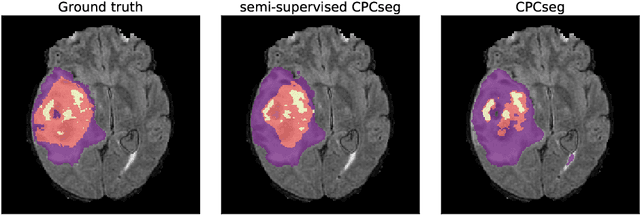

Abstract:Obtaining annotations for 3D medical images is expensive and time-consuming, despite its importance for automating segmentation tasks. Although multi-task learning is considered an effective method for training segmentation models using small amounts of annotated data, a systematic understanding of various subtasks is still lacking. In this study, we propose a multi-task segmentation model with a contrastive learning based subtask and compare its performance with other multi-task models, varying the number of labeled data for training. We further extend our model so that it can utilize unlabeled data through the regularization branch in a semi-supervised manner. We experimentally show that our proposed method outperforms other multi-task methods including the state-of-the-art fully supervised model when the amount of annotated data is limited.